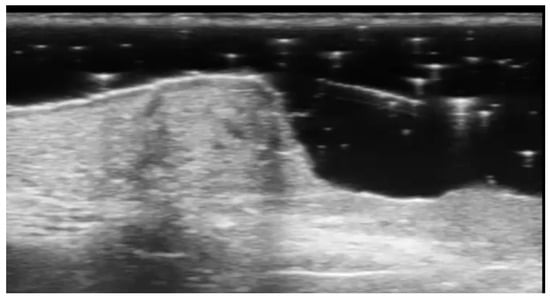

- Cheng, X.; Li, J.; Zhou, G.; Liu, Y.; Lu, X.; Wang, N.; Liu, H.; Zhang, F. High-Frequency Ultrasound in Blistering Skin Diseases: A Useful Method for Differentiating Blister Locations. J. Ultrasound Med. 2017, 36, 2367–2371. [Google Scholar] [CrossRef]